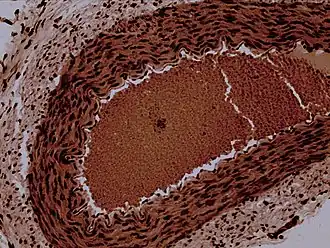

![]() Rabbit arteriole at 100X | |

Arterioles have muscular walls (usually only one to two layers of smooth muscle cells) and are the primary site of vascular resistance. The greatest change in blood pressure and velocity of blood flow occurs at the transition of arterioles to capillaries. This function is extremely important because it prevents the thin, one-layer capillaries from exploding upon pressure. The arterioles achieve this decrease in pressure, as they are the site with the highest resistance (a large contributor to total peripheral resistance) which translates to a large decrease in the pressure.[2]